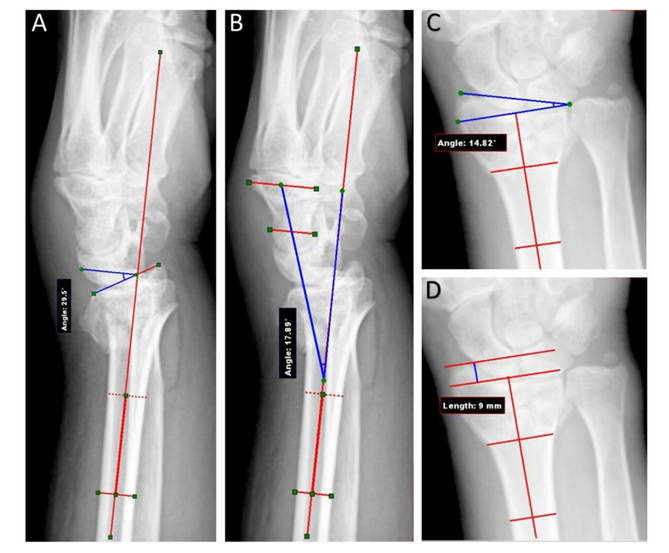

A-D术前放射学参数测量:手掌倾斜度(A)、手腕对中度(B)、径向倾斜度(C)、半径高度(D)